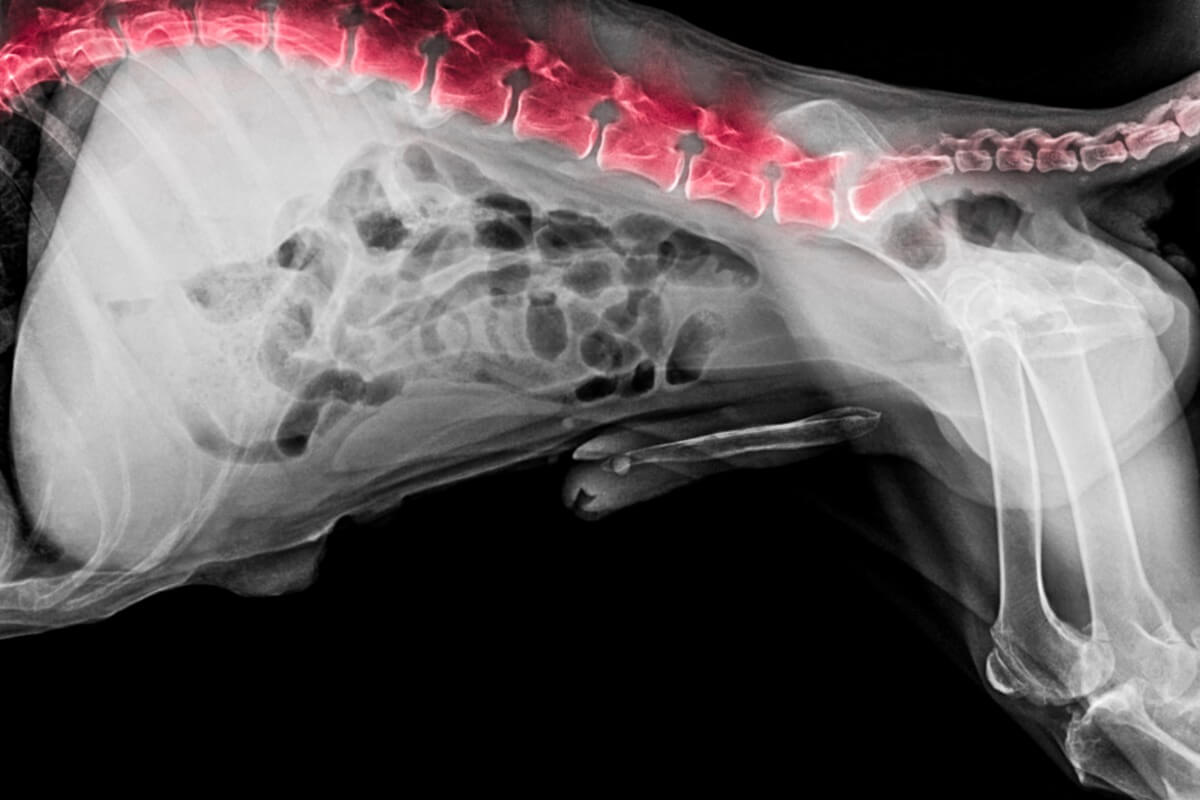

También conocida como cola de caballo o estenosis lumbosacra, la cauda equina en perros es una enfermedad degenerativa que afecta a la articulación lumbosacra, es decir, donde acaba la cadera y comienza la cola del can (vértebras L7-S1). Al degenerarse estos huesos se estrecha el canal de la médula espinal, que se ve comprimida.

En la clínica se realizan una serie de pruebas básicas para determinar la causa de la lesión. La más común es una radiografía, con la que se verifica el diagnóstico diferencial frente otras causas que pudieran manifestarse con síntomas parecidos, como tumores o fracturas. También puede ser necesaria una tomografía computarizada o una resonancia magnética.